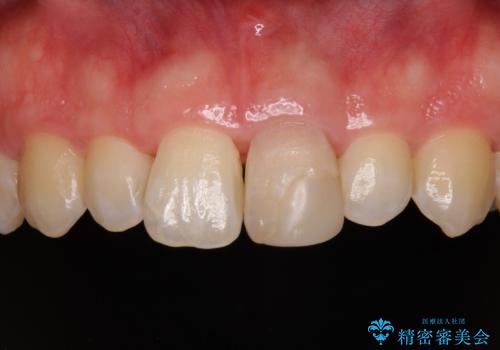

変色した前歯をオールセラミッククラウンに

- 転んだ際に欠けてしまった前歯の変色が気になるとのことで来院された患者様です。

診察やレントゲン写真より神経組織の失活が認められたため、根管治療、ファイバーコアによる土台築製後、オールセラミッククラウンにて補綴することとしました。

神経を取り除いた歯は時間とともに変色してきます。

クリーニングやホワイトニングでは改善できないため、オールセラミッククラウンなどによる補綴治療が必要となります。